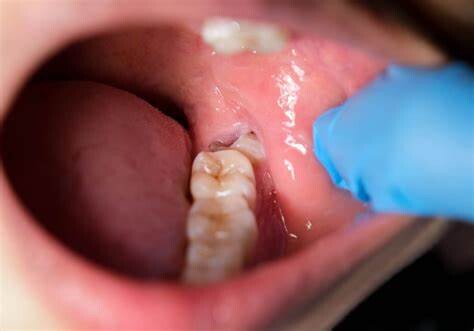

Wisdom teeth promotes Gum Disease

It is a challenging task to clean the area in which the third molars have erupted. Therefore they are at a greater risk of acquiring the periodontal problems. The gum diseases are usually caused by bacteria, and when a tooth can’t be precisely cleaned on a regular basis, the dental plaque gets accumulated around the tooth, which may lead to further complications.

Tooth Decay

The fully impacted or the partially impacted wisdom teeth are at greater risk of tooth decay, than other teeth. This usually happens, because of the location of the wisdom tooth, especially towards the back of the mouth, which is hard to clean. Moreover, since it lies at the back of the mouth, there are chances of food getting easily trapped between the gums and the tooth, promoting the growth of bacteria.